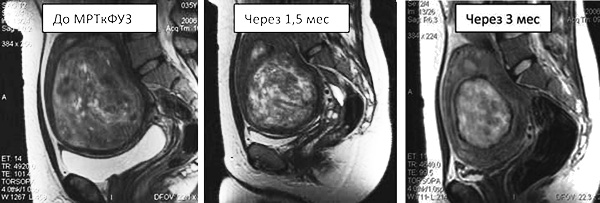

Динамика уменьшения миомы матки после ФУЗ-абляции.